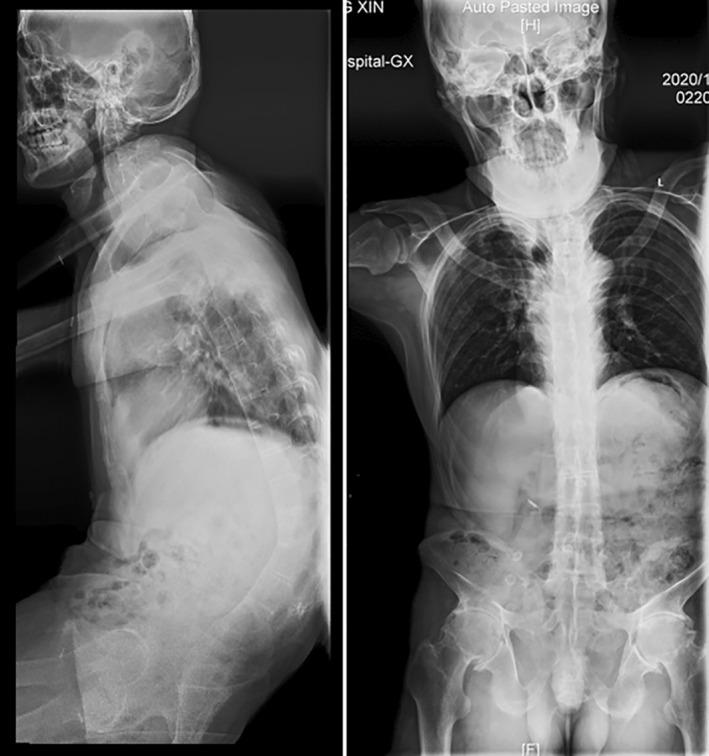

A 49-year-old male reported a 30-year history of thoracolumbar pain and limited mobility and was diagnosed with AS with dual complications of AL and ICSH. Before correction surgery, physical examination, x-ray, CT, MRI and Blood HLA-B27 examination were performed and a series of radiological parameters, including the degree of kyphosis and the T1-pelvic angle (TPA), were measured. Several days after surgery (Distal PSO was used), we performed examinations to check the patient's physical condition which showed the patient recovered remarkably. CTA was done, indicating that the patient's aorta moved anteriorly with the osteotomy side undamaged. A series of morphological parameters were measured again, including TPA, LL, and TK. CT and MRI were performed again, reflecting significant bone-to-bone fusion and successful recovery. The patient relieved the symptoms and regained his daily activities.

一名49岁男性有30年胸腰段疼痛及活动受限病史,被诊断为AS并伴有AL和ICSH双重并发症。在矫正手术前,进行了体格检查、X线、CT、MRI及血液HLA - B27检查,并测量了一系列放射学参数,包括后凸畸形程度和T1 - 骨盆角(TPA)。手术后几天(采用远端腰大肌松解术),我们进行检查以评估患者身体状况,结果显示患者恢复显著。进行了CT血管造影(CTA),表明患者的主动脉向前移动,截骨侧未受损。再次测量了一系列形态学参数,包括TPA、腰椎前凸(LL)和胸椎后凸(TK)。再次进行CT和MRI检查,显示有明显的骨对骨融合且恢复成功。患者症状缓解,恢复了日常活动。